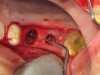

The augmentation was accessed through a crestal approach in both site Nos. 13 and 14 using a crestal approach kit (Integrated Dental Systems, www.megagenids.com). The sinus express bur was set using a built-in stopper 1 mm past the radiographic sinus floor. After the use of several hand instruments, the Schneiderian membrane was lifted, and an intact sinus membrane was observed. The osteotomies were connected through the sinus floor (Figure 9). The bone graft was placed into the sinus cavity and two implants (Integrated Dental Systems) were placed and buried (Figure 10). Four months later the implants were second-staged and the soft tissue was apically repositioned (Figure 11). The final impression was taken 2 weeks later and 10 days after that, the final crown was delivered (Figure 12).

Figure 9. Sinus curette connecting the extraction defect and crestal sinus access.

Figure 9